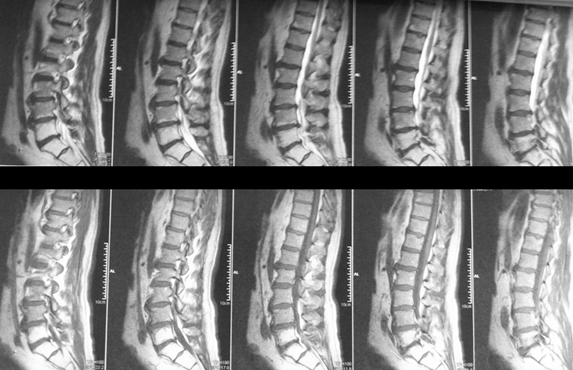

Mr B, né en 1946, a présenté en 2000 un cancer du rectum. Il a bénéficié d’une chirurgie et d’une radiothérapie. Il est lombalgique chronique mais en 2005 les douleurs deviennent lombo-sacrées et surtout d’horaire mixte.

Vous trouvez ci-dessous l’IRM de  2010.

Vous le revoyez 3 années plus tard avec les mêmes douleurs.

La nouvelle IRM est présentée ci-dessous.